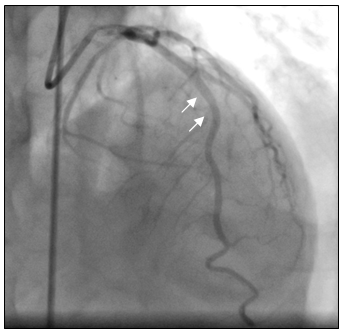

Tại phòng thông tim huyết áp bệnh nhân thấp 80/60mmHg nên chúng tôi không dùng Nitroglycerin. Sau khi chụp thấy hẹp nặng lan tỏa ở cả ba nhánh của động mạch vành, không loại trừ do co thắt nên chúng tôi đã tiến hành bơm 500µg Nitroglycerin vào động mạch vành. Kết quả chụp lại hiện tượng trên hoàn toàn biến mất, động mạch vành phải và trái thâm nhiễm nhẹ nhưng đều có kích thước lớn hơn nhiều so với ban đầu, dòng chảy TIMI 3 (hình 3a-3b), đồng thời huyết áp của bệnh nhân cũng cải thiện rõ 120/80 mmHg.

Hình 3b: Nhánh RCA sau khi bơm Nitroglycerin.